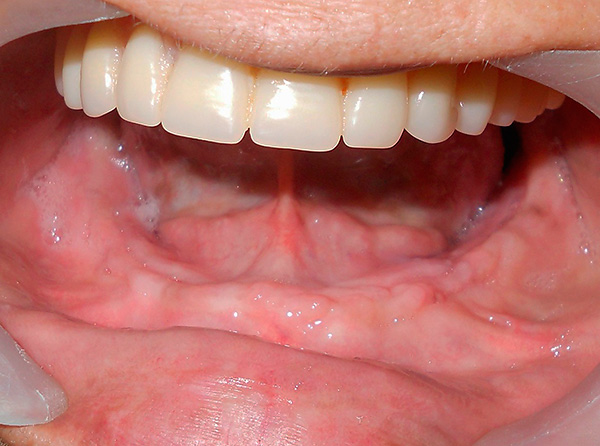

O último estágio do implante basal é a prótese. Após a instalação dos implantes basais, a prótese é geralmente colocada por 2-3 dias - para criar a carga primária necessária. A prótese é feita com moldes removidos da mandíbula do paciente. Ao mesmo tempo, todos os implantes instalados são impressos na impressão, cuja relação espacial já é estudada pelo técnico em odontologia nos modelos obtidos, que faz a prótese necessária no laboratório odontológico (ao mesmo tempo, são levados em consideração os dados do modelo de computador criado na fase preliminar).

As próteses imediatas (imediatas) desempenham um papel muito importante em todo o processo de tratamento.

Primeiramente, a prótese transfere imediatamente a carga mastigatória para os implantes e, através deles, para o tecido ósseo, devido ao qual processos naturais são ativados nela, e a regeneração prossegue o mais rápido possível. Simplificando, o osso é restaurado rapidamente em muitos aspectos, devido ao fato de o paciente poder mastigar alimentos alguns dias após o implante basal.

Em segundo lugar, a prótese conecta todos os implantes instalados em um único design. Se um implante estiver muito carregado, ele será deslocado sob carga. Porém, devido ao fato de a estrutura da prótese unir todas as raízes artificiais, elas ficam imóveis e calmamente se enraízam no tecido ósseo, apesar da presença de intensa carga mastigatória.

Em terceiro lugar, a prótese permite que o paciente se sinta pleno - a estética e a possibilidade de nutrição são restauradas com implante basal quase que imediatamente.

No entanto, há um ponto muito importante (que alguns podem considerar um sinal de menos). Embora após a instalação dos implantes a prótese seja fixa permanente, não removível, mas ainda assim seja uma estrutura temporária. Isso significa que você precisa usá-lo por pelo menos seis meses e, na prática - até 3-4 anos, até as coroas plásticas falharem e perderem a aparência. Após a prótese, você terá que substituí-la por uma permanente - ou seja, uma que permaneceu inativa por décadas.